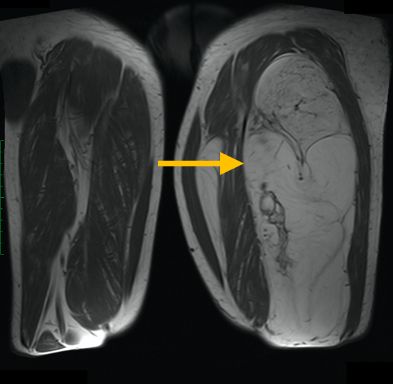

Radiographic imaging is used to help form a diagnosis of liposarcoma. These include X-Ray, MRI, CT and Bone Scans

An example of an MRI is shown.